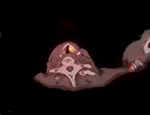

Left vocal cord palsy with Teflon injection. Axial CT (A), PET (B), and PET-CT fused (C) images show intense FDG activity within the left vocal cord from the inflammation caused by the Teflon. |

| Left vocal cord palsy with Teflon injection. PET-CT fused (C) image shows intense FDG activity within the left vocal cord. |